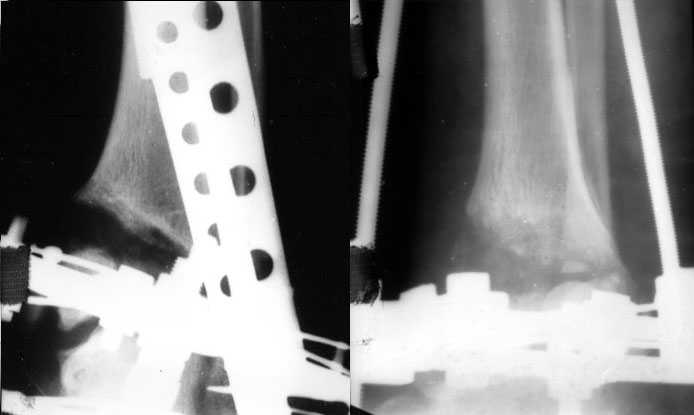

Аппаратом можно сделать все минимально инвазивно и травматично, вырастить клиновидный регенерат после чрескожной остеотомии через один или два разреза 0,5 см. В приложении похожий по локализации случай, только более давние последствия травмы с замыканием части зоны роста, деформация побольше, плюс укорочение голени было.

Померять однозначно сложно. Зато операция с аппаратом проще и быстрее. Провел-собрал-через прокол рубанул-1 шов-иди отдыхай. А открыто - и клиновидный дефект одномоментно может получиться большой, и очень короткий дистальный отломок фиксировать не очень будет удобно, потом на итоговых снимках вдруг обнаружится, что уголок не совсем такой, как планировали... Про другие возможные проблемы вспомнить можно...

Есть возможность аппаратом все исправить, а потом перейти на внутреннюю фиксацию.